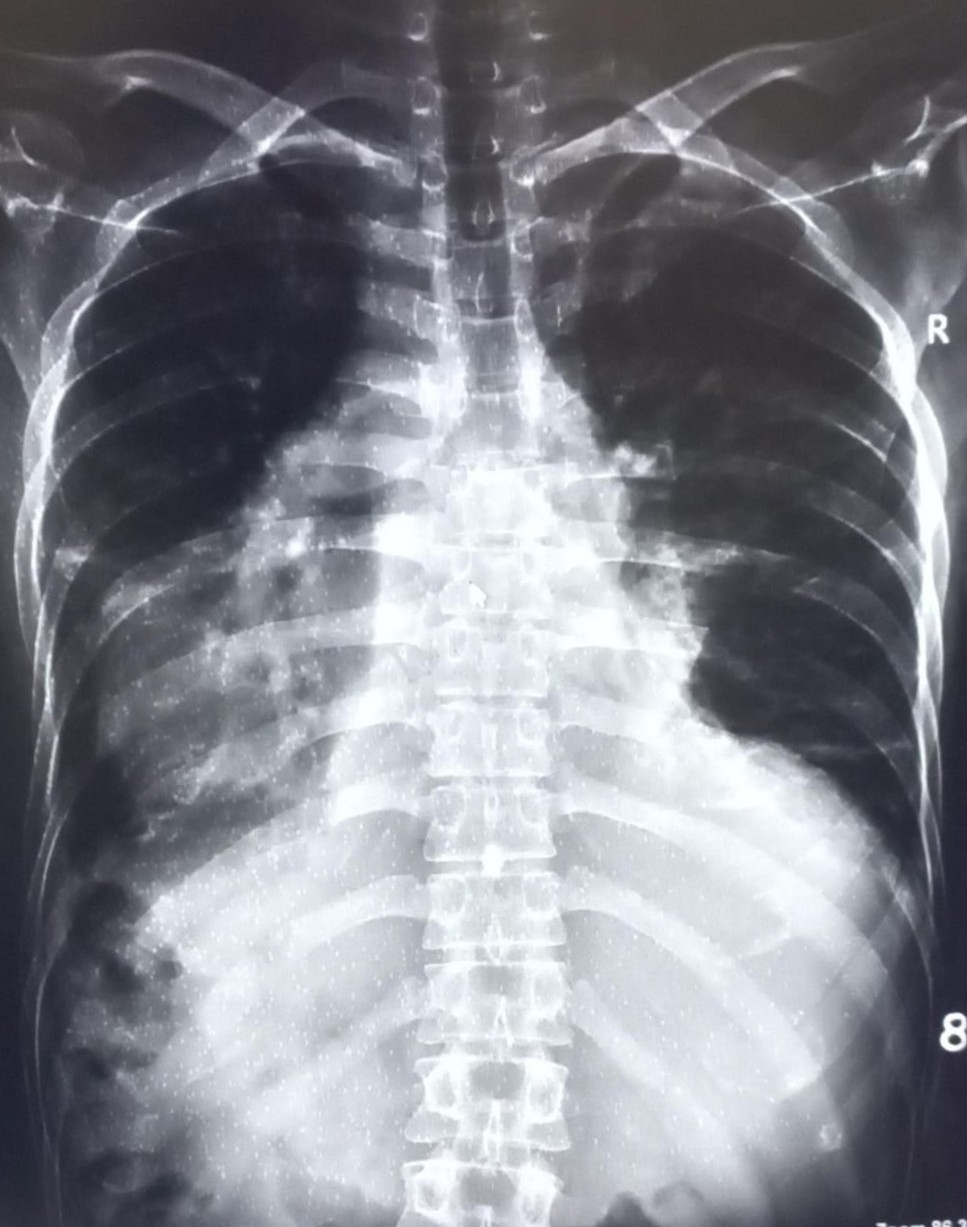

| 4440 | IGGMC, Nagpur, Nagpur | P2 | 29-32 | kamal dasar | Consent taken on Paper | 49 Yrs. |

Provisional Diag : cough under evaluation

Final Diag : OBLITERATION OF LEFT CP ANGLE BLUNTING/LEFT SIDED PLEURAL EFFUSION |

Non-TB Case (Confirmed) | OBLITERATION OF LEFT CP ANGLE BLUNTING/LEFT SIDED PLEURAL EFFUSION | Abnormality visible on x-ray |